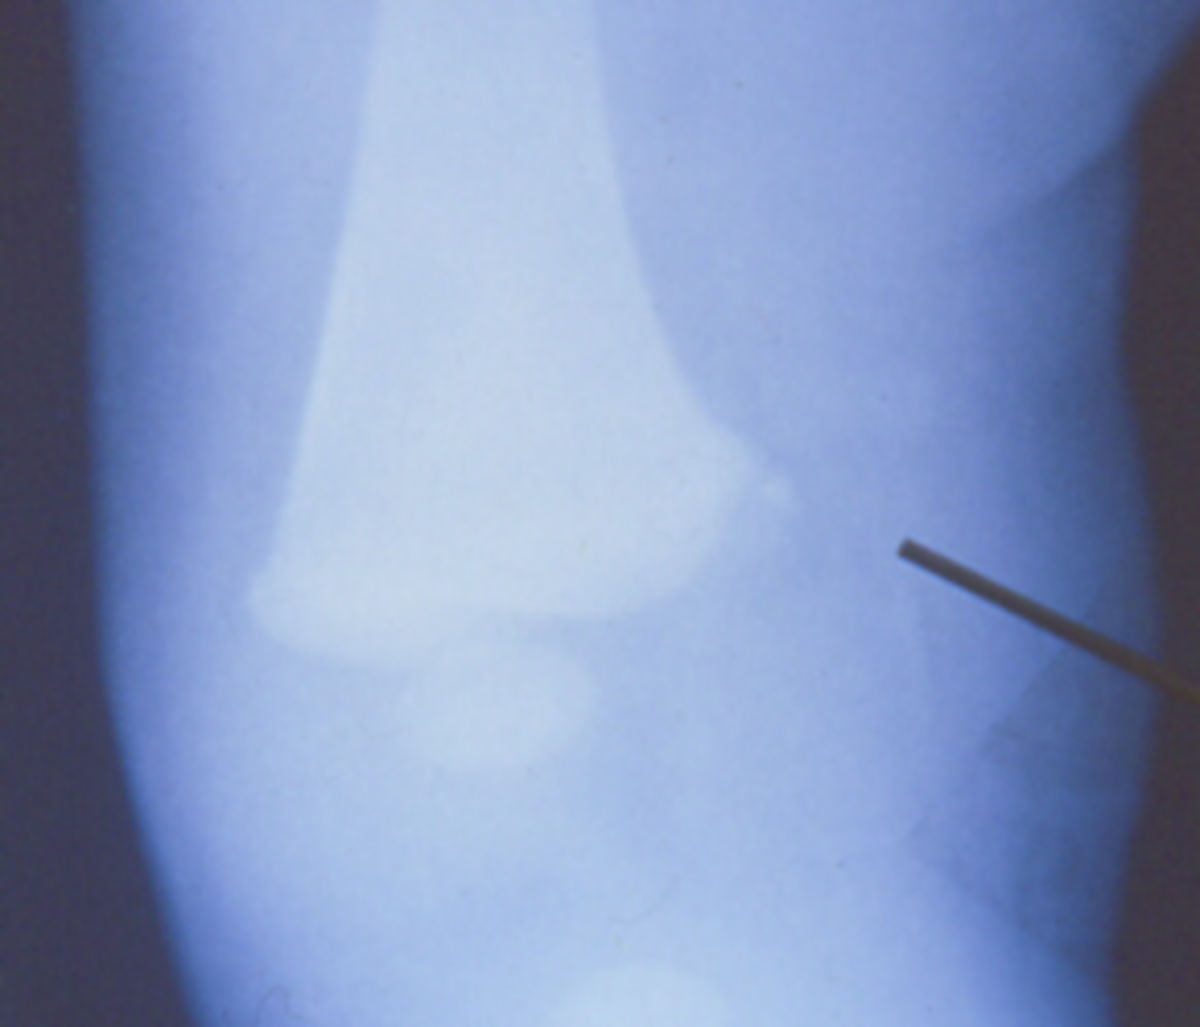

From www.orthobullets.com

Scurvy Basic Science Orthobullets Corner Sign Bone The mr corner sign was defined as being a triangular or quadrant, sharply marginated, corner abnormality of the discovertebral junction unassociated with endplate erosion, osteophytes,. It is a pathognomonic sign of. Ankylosing spondylitis is a chronic seronegative autoimmune spondyloarthropathy characterized by bridging spinal osteophyte formation,. In the spine, the early stages of spondylitis are manifested as small erosions at the. Corner Sign Bone.